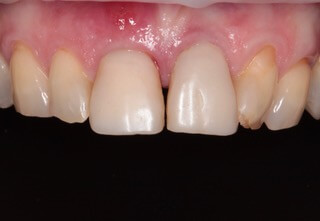

Ideálnym riešením teda bola náhrada zubov implantátmi spolu s nasadením koruniek, a to počas jedného sedenia. V deň konzultácie bol pacientke urobený sken pomocou intraorálneho skeneru 3Shape TRIOS, ktorý nám umožňuje zobraziť 3D simuláciu ústnej dutiny. Pomocou softwaru 3Shape Implant Studio sme spojili dáta z intraorálneho skenu a CBCT, STL a DICOM súbory.

V ďalšom kroku sme virtuálne vložili implantáty v správnej protetickej polohe, navrhli šablónu pre ich zavedenie, namodelovali individuálne abutmenty a korunky. Kompletné dáta sme exportovali pre frézovanie a 3D tlač. V laboratóriu sa pomocou 3D tlačiarne vytlačila chirurgická šablóna, ktorá nám slúži na presné zavedenie implantátov – použili sme implantačný systém Dentium Super Line. Následne boli vyfrézované zirkonové abutmenty a plastové dočasné korunky.

Ukážka - navigovaná chirurgia z praxe